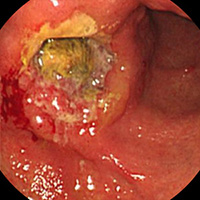

캔디다 식도염

• 캔디다 감염증에 의해 발생한 식도염을 캔디다 식도염이라고 합니다. 보통 면역억제제 및 광범위 항생제나 스테로이드를 사용할 때, 당뇨병, 알코올 중독증, 영양결핍, 고령 등으로 면역 기능이 감퇴하였을 때 자주 발생합니다. 캔디다 식도염은 내시경검사에서 식도 점막에 다발성의 흰색 또는 황색 플라크(plaque)가 부착되어 있는 모양을 보고 쉽게 진단 할 수 있습니다.